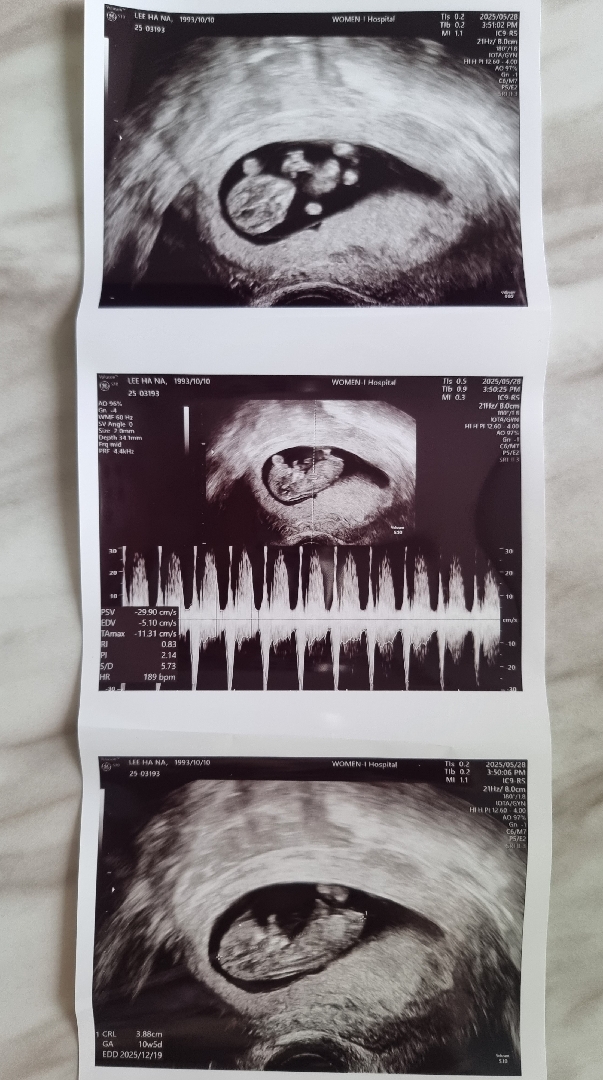

딸일까용 아들일까용 각도법궁금해요

초음파사진은 10주차 사진이구요 12주때갔더니 선생님이 다리사이에 뭐가 보인다고하던데 12주 성별은 정확하지 안을까요~~?

10주차에는 각도법이안보여요..🥲